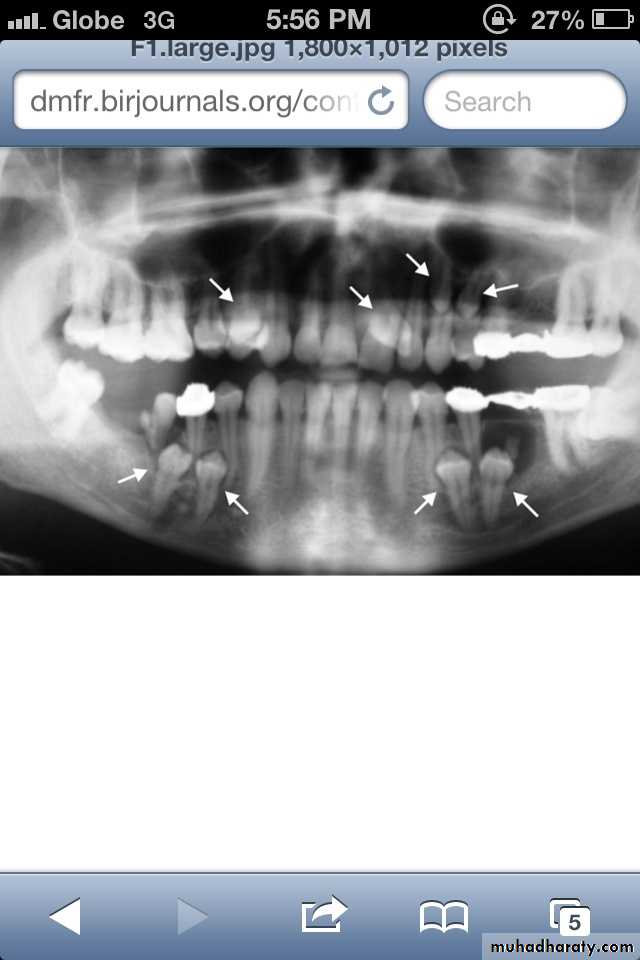

Paramolar blocking the eruption of 3rd molar.

MesiodensDistomolars(4th molar)

Mesiodens

Distodens or distomolarParamolar

Supplemental

Many supernumerary teeth never erupt, but they may delay eruption of nearby teeth or cause other dental problems.